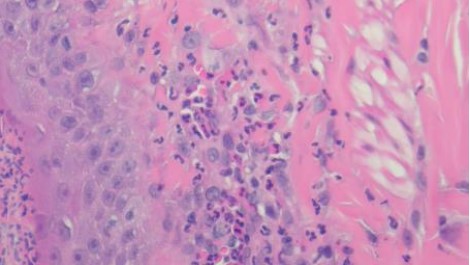

組織病理結果為化膿性嗜酸球性真皮炎,如圖四所示。排除感染的問題,提高prednisolone劑量到3mg/kg sid,兩週後硬皮病灶消失、搔癢症狀緩解,開始逐漸減量類固醇,目前1mg/kg qod狀況良好如圖五所示,持續治療。

A B

C D

圖四:A, 檢體為表皮層到真皮層組織,少部分表層皮下脂肪有涵蓋在檢體內。B, 表皮結構完整,表面有大量的壞死細胞碎片、片狀角質、脫落的角化細胞覆蓋或是形成沒有破裂的膿皰結構,皮膚糜爛但局限於表皮,基底膜完整。C, 真皮層輕微水腫,有少量到中等量、零散分布的發炎細胞浸潤,細胞有略微分布表層真皮或是毛囊腺體周圍的傾向,但不明顯。D, 浸潤的細胞以嗜中性球、嗜酸性球以及肥大細胞為主,血管內也可見到數量明顯增加的嗜中性球及嗜酸性球,皆為分化成熟沒有惡性特徵。D, 表皮層中有見到一顆凋亡細胞 (apoptotic cell),但周邊沒有淋巴細胞包圍。E, 此外毛囊腺體的結構完整,沒有破裂,毛囊內也沒有見到細菌、黴菌或是寄生蟲。以特殊染色B&B檢查檢體,沒有見到細菌病原。